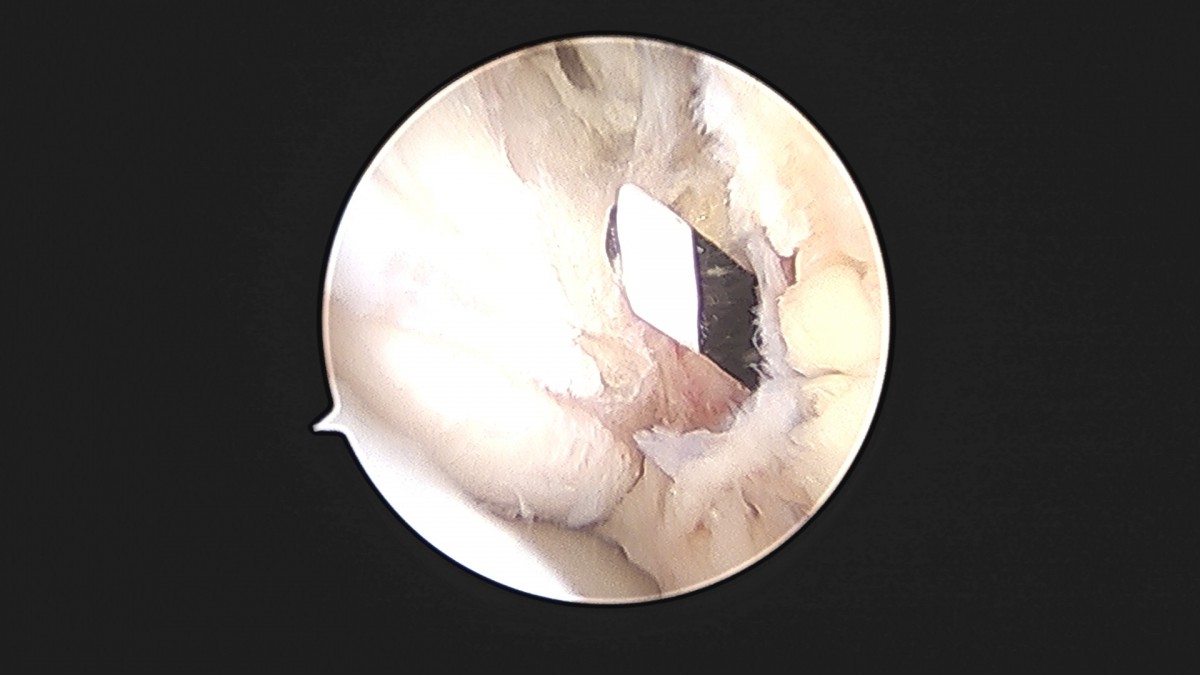

이재상원장님 발목 인대 봉합술 이주O 환자

dae765e4d9ac96aee867c9d6292d8784_1758007209_4929.jpg